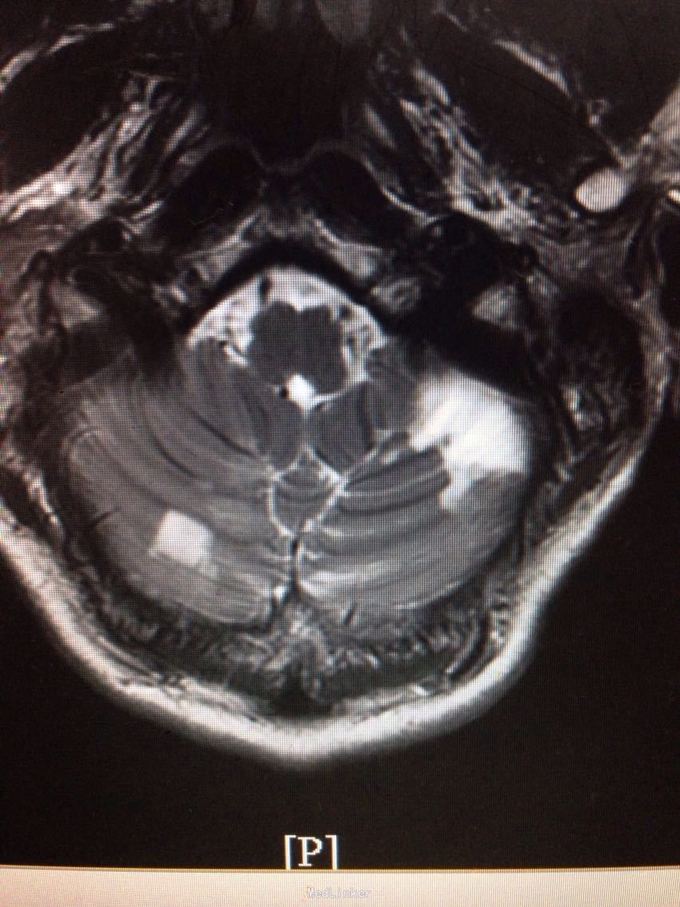

患者为59岁男性,因头晕、头痛、行走不稳7天入院。患者缘于7天前无明显诱因感头晕,伴视物旋转、视物模糊、恶心,静坐约20分钟可缓解,伴头痛,右侧肢体乏力,行走不稳,症状反复。遂来我院。既往有高血压病史。

查体:双侧瞳孔等大等圆,直径2mm,双眼左视可见震颤,Romberg征阴性,跟膝胫试验欠稳准,NIHSS评分3分,洼田饮水试验1级。 我院急诊头颅CT示:双侧小脑半球片状低密度影,考虑脑梗塞。 颅脑MRI示:双侧小脑半球多发急性脑梗塞,以右侧为著。

诊断为脑梗死(急性期,双侧小脑半球) 治疗上予双抗血小板,改善循环,营养神经,清除自由基及降脂稳定斑块等治疗。